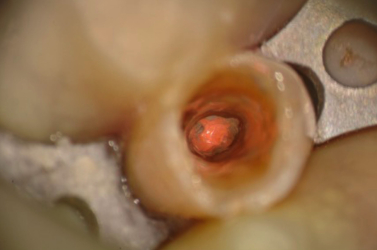

Close Up View

Close Up View

Close Up View of GP and Rotary File

GP Fragments in Canal at High Mag

Note Small Amount of GP in Canal Under Scope